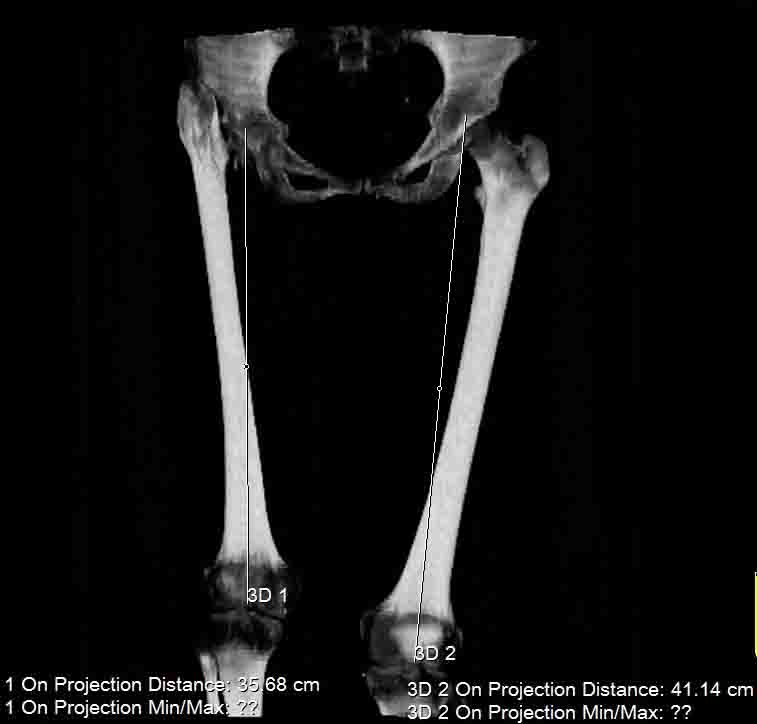

Поскольку основная жалоба на укорочение конечности, то я ей предложил удлинить голень. Величину удлинения обсудили - в пределах 4 см.

Сделал ей КТ.

С удивлением узнала, что перелом в области шейки у неё не сросся, хотя на рентгенограмме тех лет так оно и есть.

Интересна функциональная адаптация - практически полная функция того, что раньше было тазобедренным суставом.